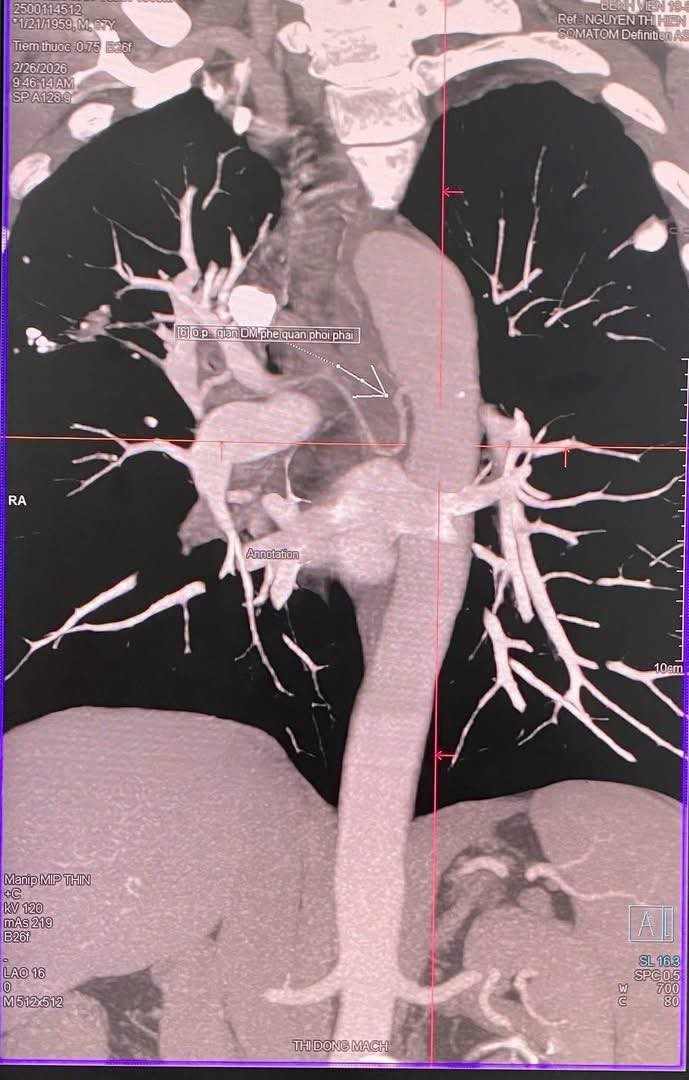

Sau hội chẩn chuyên môn, ngày 27/2, ê-kíp quyết định thực hiện can thiệp nút động mạch phế quản dưới hướng dẫn DSA – phương pháp can thiệp mạch ít xâm lấn, hiệu quả cao.

Hình ảnh giãn phế quản động mạch phải trên phim chụp - Ảnh BVCC

Ca can thiệp được thực hiện bởi ThS.BSCKII Lê Hồng Kỳ, Trưởng khoa Chẩn đoán hình ảnh và y học hạt nhân cùng ê-kíp can thiệp mạch giàu kinh nghiệm.

Kết quả, thủ thuật thành công, kiểm soát hoàn toàn nguồn chảy máu.